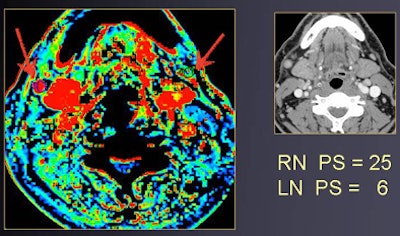

| Round shape (contrast-enhanced CT, above) suggests suspect nodes in a patient with right-sided oral cancer. At perfusion CT (below), relative blood volume and permeability surface area product values of right lymph node are elevated compared to the contralateral side, showing hyperperfusion. Histopathology confirmed the malignancy. All images courtesy of Dr. Agneistsa Trojanowska. |